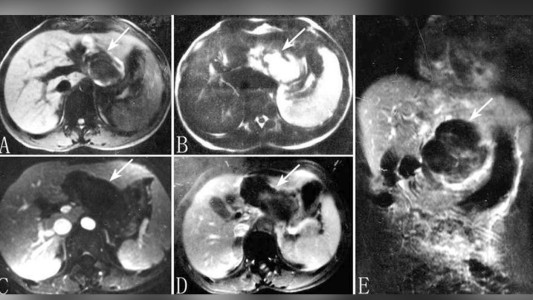

Un hombre de 67 años fue al hospital por una hernia y descubrieron que tenía órganos genitales femeninos